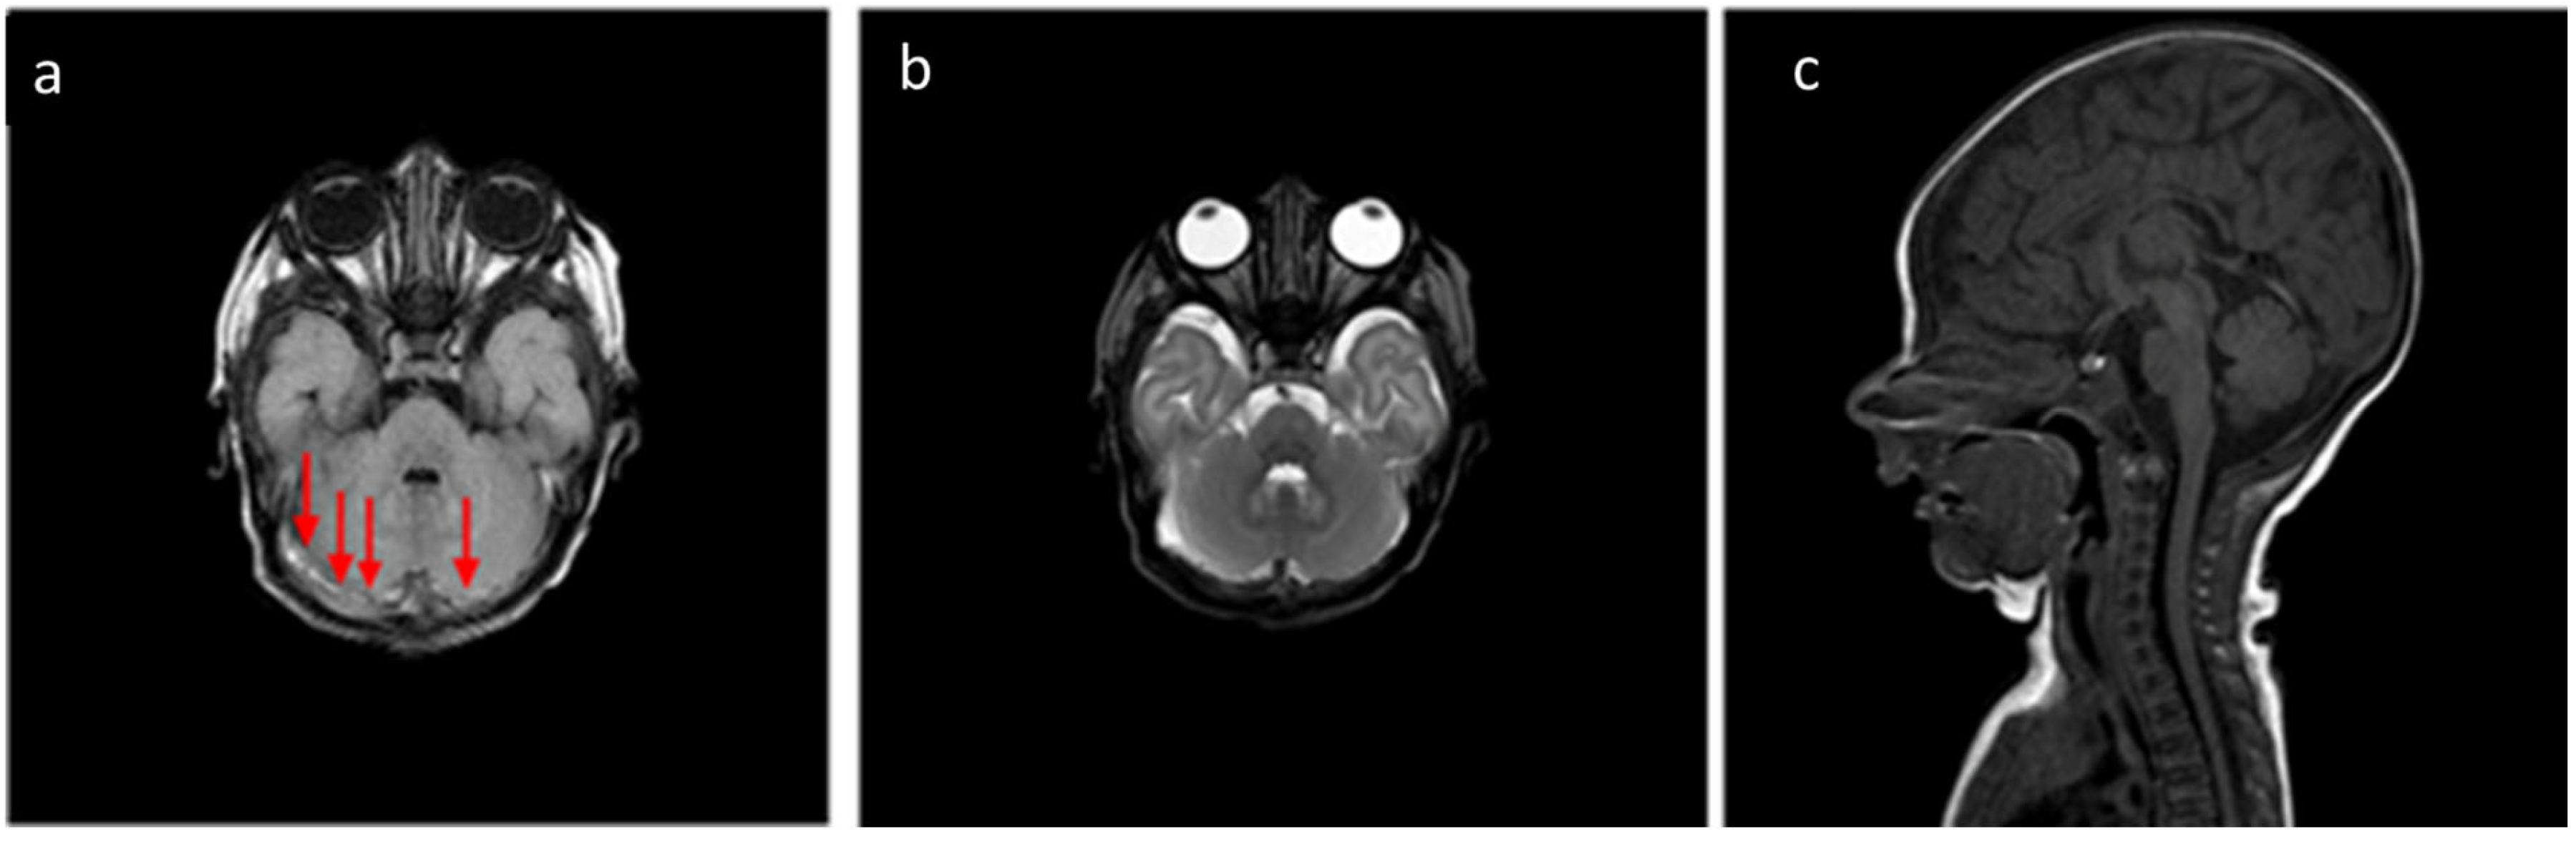

| Cerebellum | 31/32 | 96.9% |

| Cervical and Dorsal Spinal | 4/32 | 12.5% |